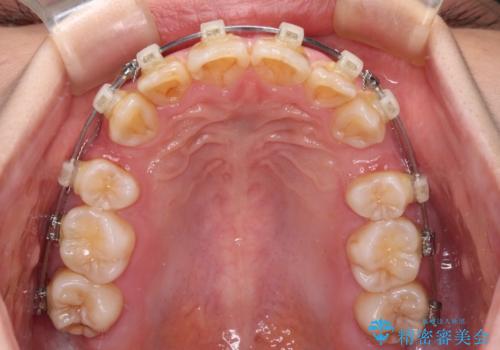

【モニター】出っ歯と八重歯 抜歯矯正でスッキリとした口元に

- クリアブラケット

- 前方に飛び出した前歯と、下顎の八重歯を気にして来院された患者様です。

口元の突出感を改善するため、上下左右の第一小臼歯4本を抜歯し、ワイヤー装置にて矯正治療を行うこととしました。

抜歯矯正により、口元の印象だけでなく、横顔の印象も大きく改善されました。